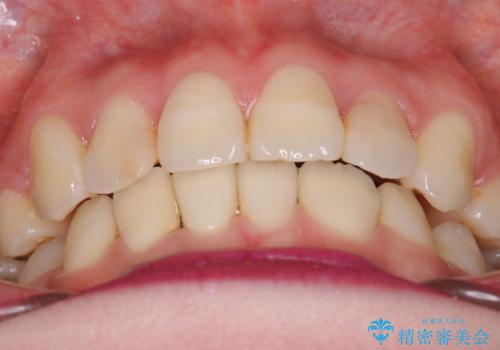

八重歯のワイヤーによる抜歯矯正 矯正治療と並行してセラミック治療も

- 八重歯と前歯のガタガタを主訴に来院されました。

左下の奥歯がすでに1本抜歯されており、ブリッジを装着されていました。

ブリッジを除去して、左下以外の上顎両側と右下の歯を合計3本抜歯して矯正する計画としました。